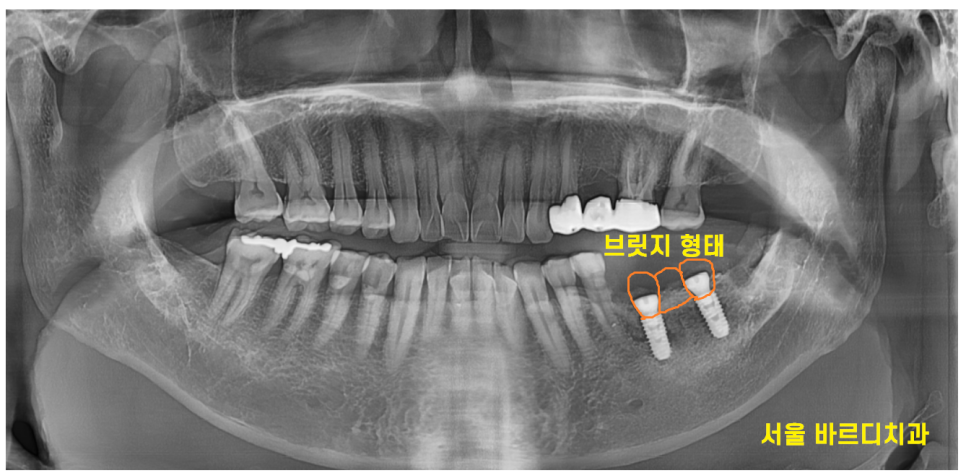

23.07.04

기존 처럼 사랑니 부분에 임플란트를 심고

브릿지 형태로 만들어 드릴 수도 있어서

환자분께 충분한 설명을 진행